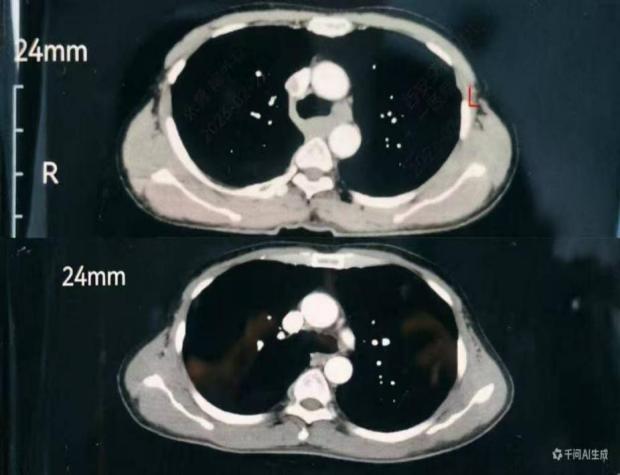

一是极致微创,创伤降至最低。摒弃传统多切口模式,实现胸部无切口,仅在颈部、腹部各做3 - 5cm微小切口,借助高清腔镜精准完成手术,减少组织损伤,减轻患者术后疼痛,降低并发症风险。

此次成功开展“胸部无切口、颈腹3-5cm小切口、颈腹同步操作”的颈腹同步双单孔微创食管癌根治术,是交大一附院胸外科在微创外科领域的重要突破,为食管疾病微创治疗提供了可借鉴推广的实践路径。